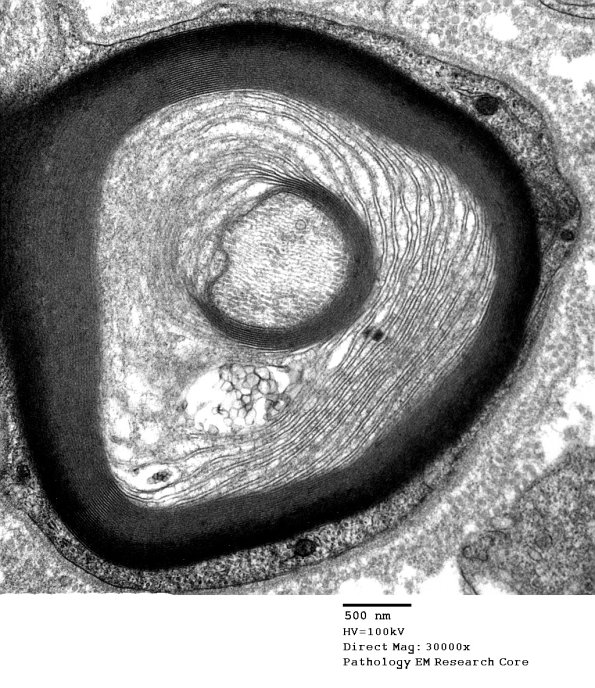

Several magnifications of the UCM in this lesion are demonstrated as well as a hemidesmosome like focus. (electron micrographs)